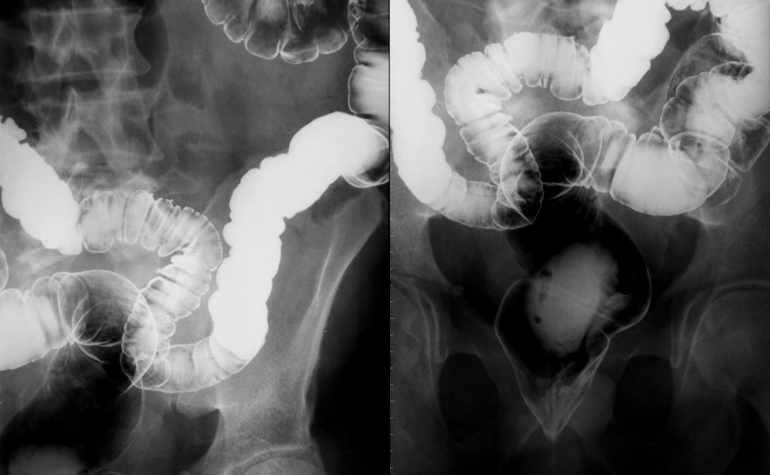

Deux méthodes de dépistage existent, qui réduisent avec la même efficacité la mortalité due à ce cancer, poursuit le professeur Cornuz. Toutes deux reposent sur le principe qu’une majorité des cancers colorectaux se développent lentement et évoluent par étapes, souligne le Dr Michael Montemurro, oncologue au Centre hospitalier universitaire vaudois (CHUV). Première méthode: la recherche de sang dans les selles pratiquée tous les deux ans (voir infographie). La deuxième méthode consiste à réaliser d’emblée une coloscopie, et à la répéter tous les dix ans entre 50 et 69 ans. On examine par cet examen l’intérieur du côlon à l’aide d’un endoscope, sorte de tuyau souple introduit par l’anus et dont la caméra envoie des images au médecin. C’est la première méthode, la recherche de sang dans les selles, qui a été proposée jusqu’à mi-avril dans les pharmacies suisses. «Le patient recevait un kit permettant de prélever, à la maison, un échantillon de selles. Il devait ensuite l’envoyer par la poste à un laboratoire pour une recherche d’éventuelles traces de sang. En effet, le plus souvent les lésions qui conduisent au cancer colorectal saignent, même de manière microscopique», explique le professeur Gian Dorta, gastro-entérologue au CHUV.

Comme tout examen, ces tests dits «Fit» ne sont pas parfaits et présentent un risque d’erreur. Dans 2 à 4% des cas, ils ne détectent pas un cancer alors qu’il est bien présent. Pour cette raison, le Fit est renouvelé tous les deux ans dans les programmes de dépistage. On peut donc raisonnablement imaginer qu’un cancer «manqué» lors d’un premier test Fit serait repéré et traité deux ans plus tard. «En cas de test Fit positif, une coloscopie doit être réalisée dans les trois à quatre semaines», détaille encore le professeur Dorta. L’examen nécessite une préparation. «Le patient doit consommer peu de fibres durant trois jours et boire un litre d’un liquide au goût pas forcément agréable la veille et le jour de l’examen, détaille le médecin. Cela provoque une diarrhée qui nettoie le côlon; sans quoi nous ne pourrions rien voir.» Durant l’examen lui-même, le patient est sous sédation. La coloscopie a l’avantage de permettre de faire des biopsies d’éventuelles zones suspectes et parfois de les supprimer. En particulier, le gastro-entérologue recherche des polypes, c’est-à-dire des excroissances de la muqueuse qui pourraient devenir des cancers. Ou en être un à son début. Les polypes varient en nombre, en diamètre et en localisation selon les individus, détaille le professeur Dorta: «On estime que 20 à 25% de la population de plus de 50 ans ont de tels polypes, poursuit le spécialiste. Et que parmi eux, 20% environ évolueront vers un cancer.»